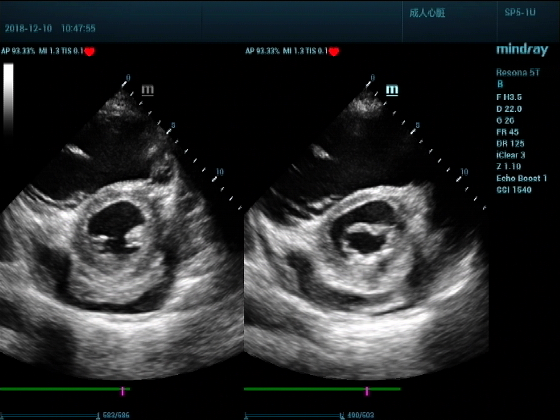

病例二:

男,81岁,全身浮肿来住院

超声可见:左房,右房,右室明显增大,主肺动脉及右肺动脉增宽,二尖瓣中度反流,三尖瓣重度反流,肺动脉轻度高压,心律不齐

心包积液盆腔积液。淤血性肝增大,肝静脉增宽。(右心衰声像改变)